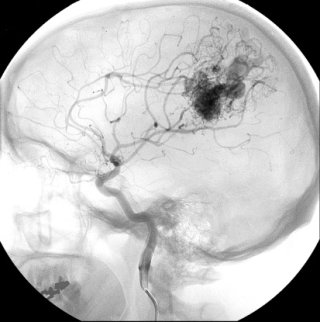

뇌출혈이 의심되면, 신속한 영상 검사가 필수예요. 비(非) 조영 CT 스캔이 가장 먼저 시행되며, 출혈 여부와 양을 확인할 수 있어요. 필요하다면 CT 혈관 촬영(CTA)이나 MRI, 뇌혈관 조영술 등을 추가해 출혈의 원인과 혈관 구조 이상 유무를 평가하죠. 또한, 혈액 검사로 응고 상태, 혈소판 수치, 항응고제 복용 여부 등을 확인해 치료 계획을 세우는데 중요한 참고 자료로 활용돼요.